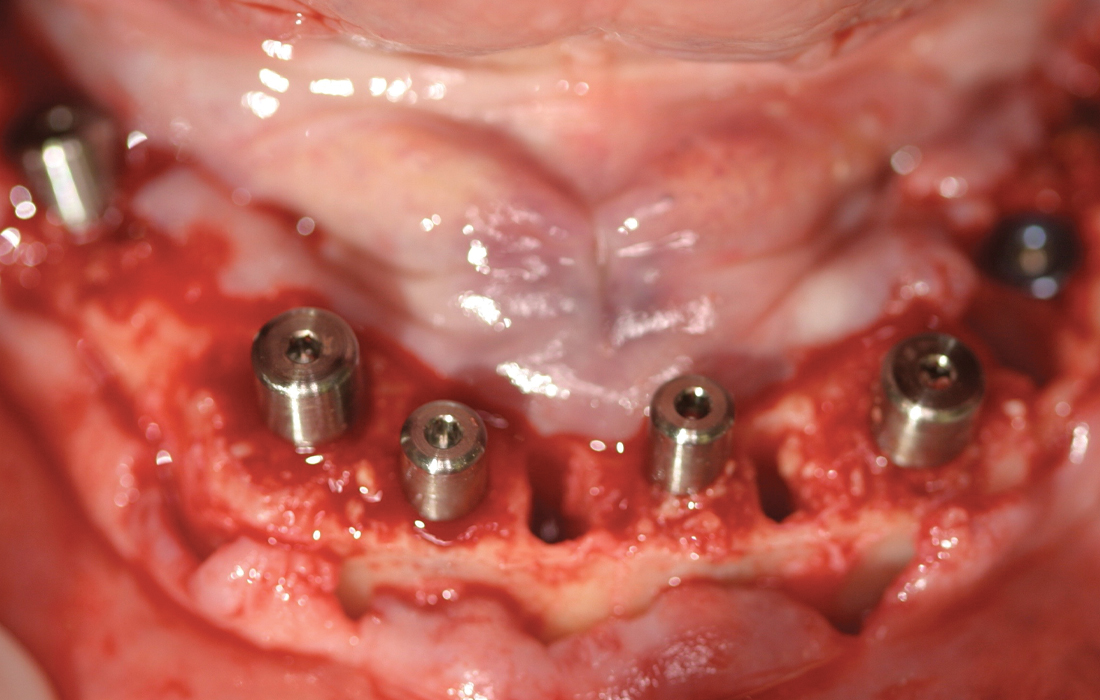

This patient presented with terminal dentition due to extensive caries and advanced periodontal disease. After removing the patient’s remaining teeth, Hahn Tapered Implants were placed during the same appointment to support a fixed restoration, and healing abutments were delivered. Four months later, a monolithic zirconia full-arch restoration was delivered, providing the patient with renewed function, esthetics and quality of life.